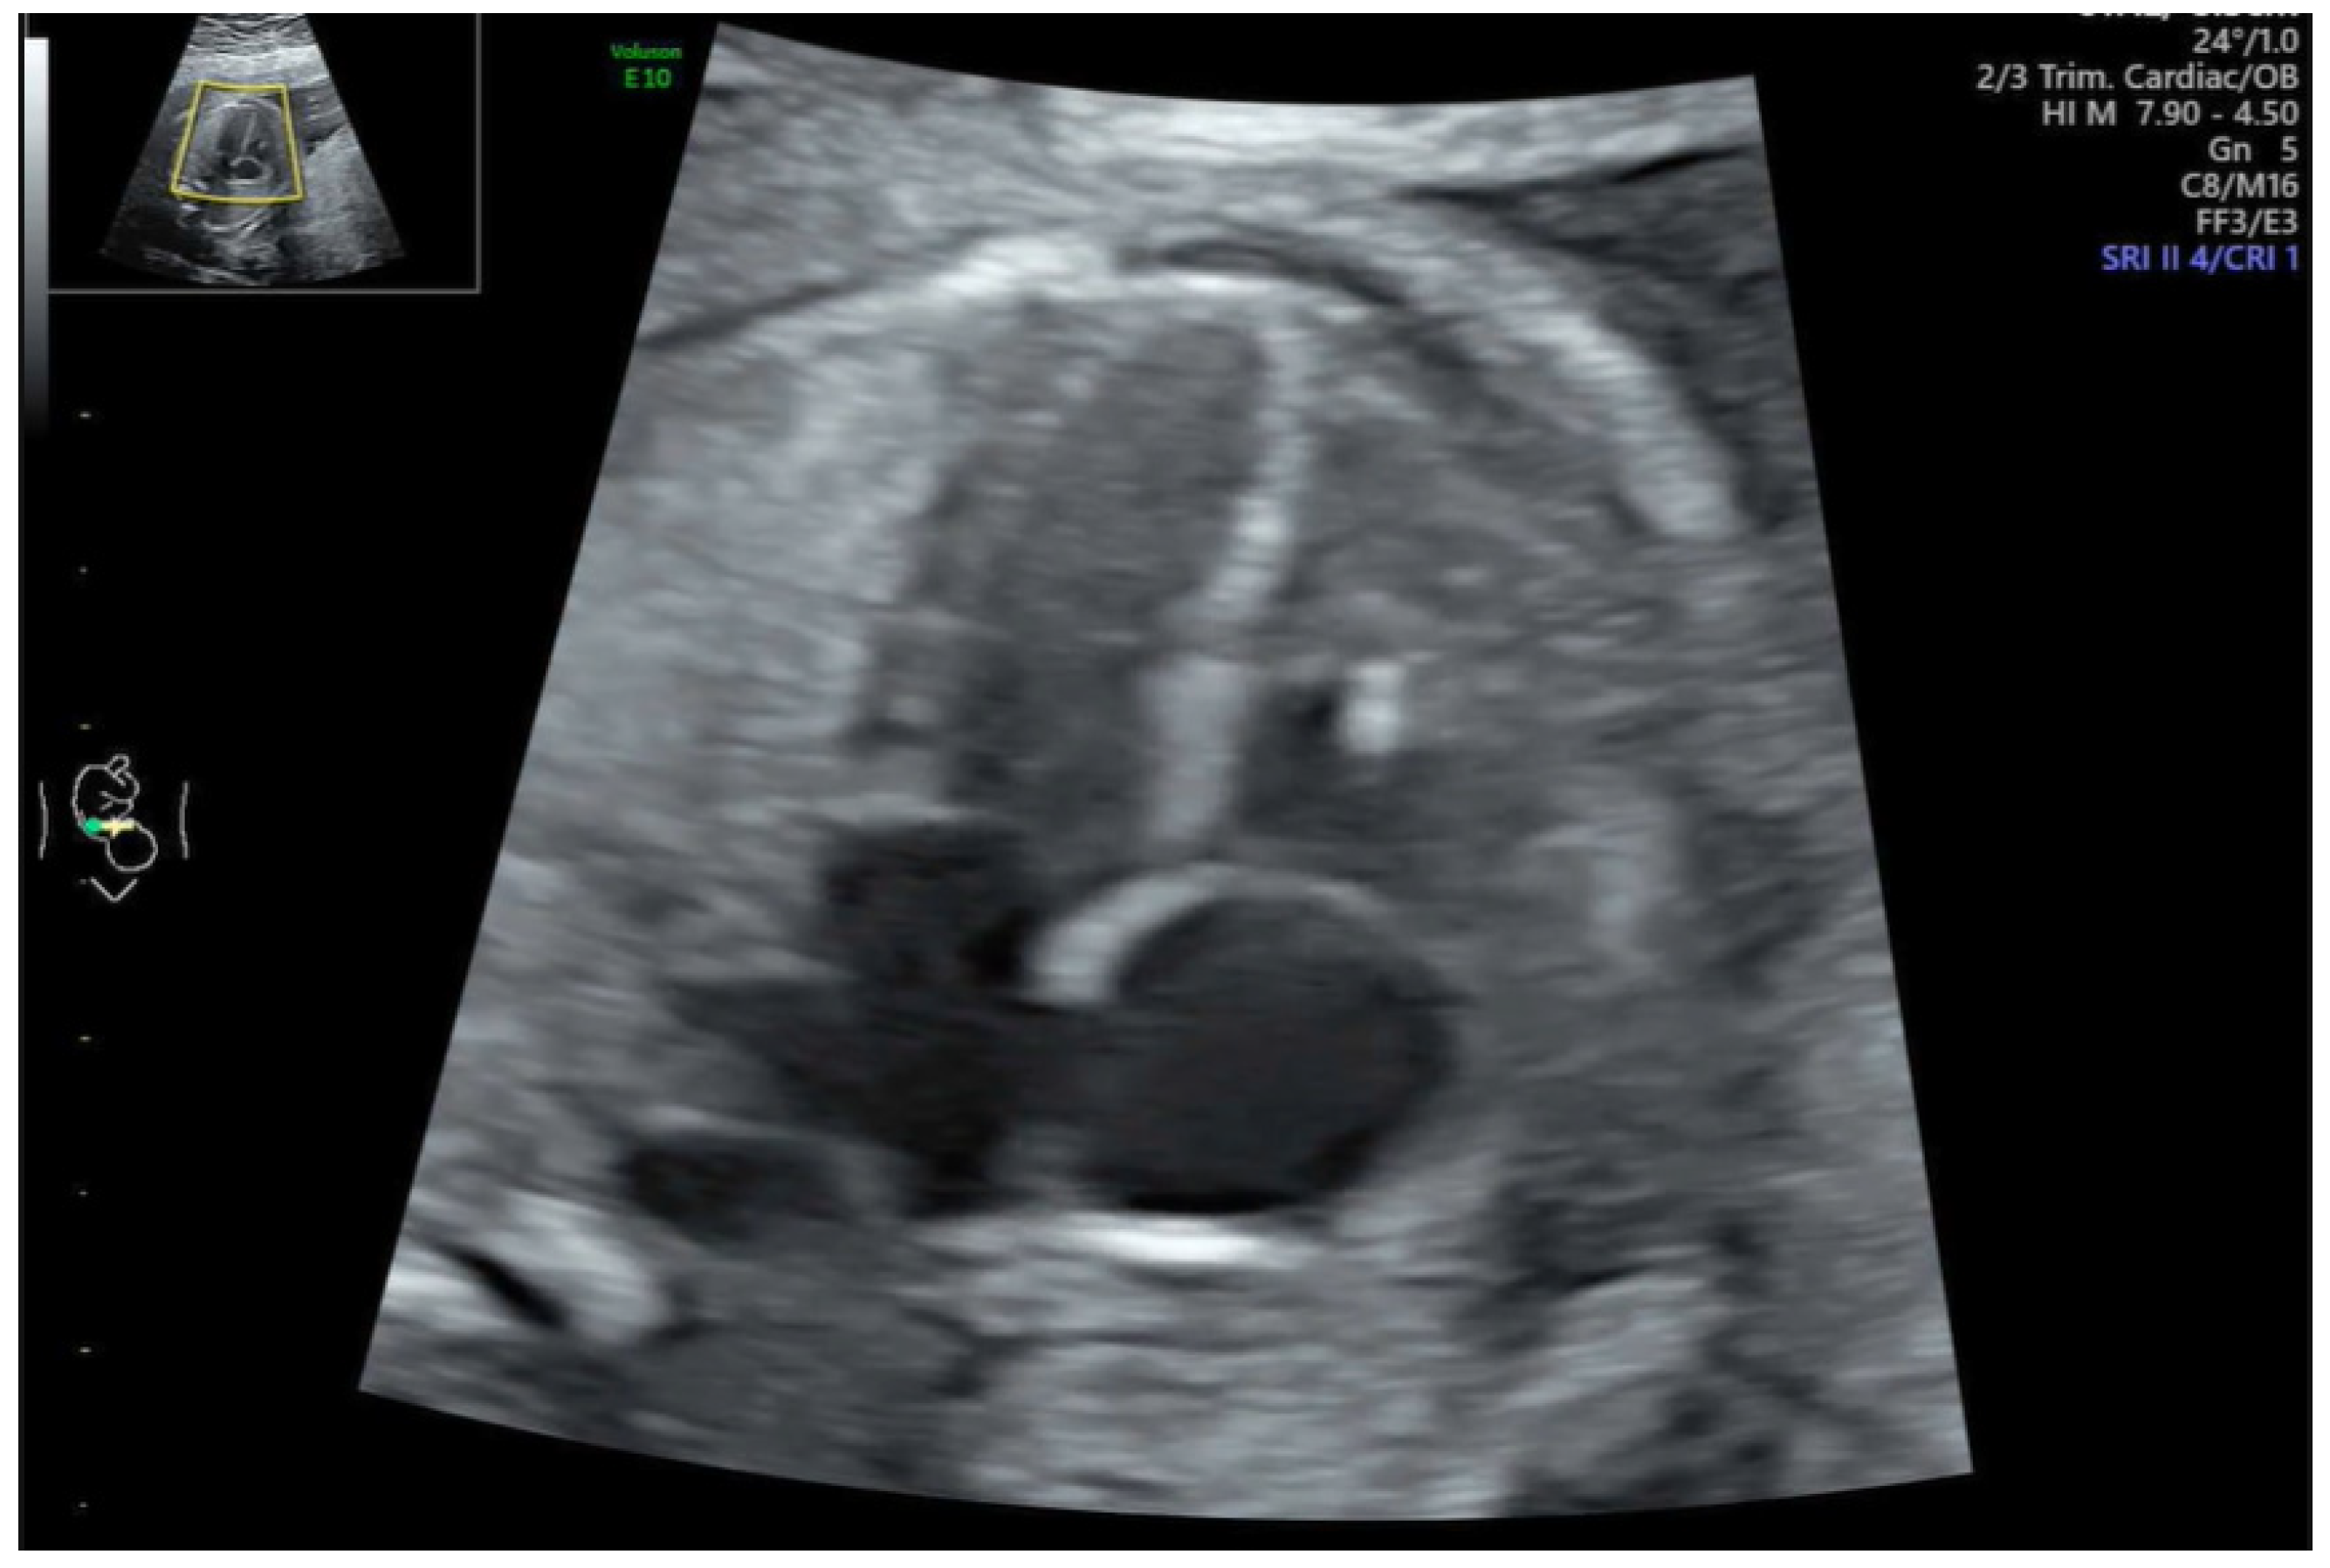

2.1. Defining of Functional Abnormalities